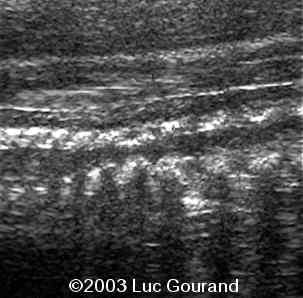

Radiohumeral ankylosis was seen at the level of the arm, the thumb and toes are broad.

case0093-14

case0093-15

Abnormal vertebrae.

case0093-17